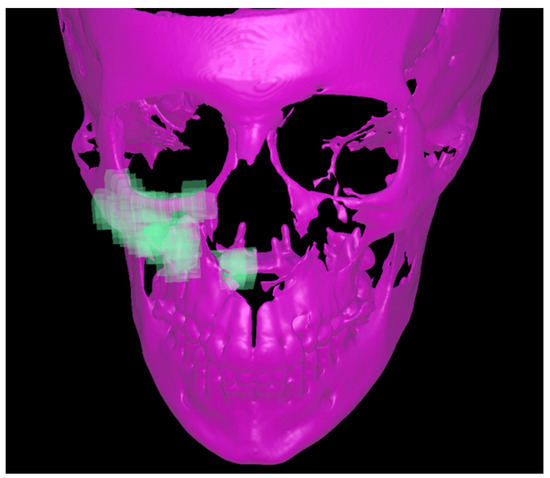

- Cantarella, D.; Dominguez-Mompell, R.; Moschik, C.; Sfogliano, L.; Elkenawy, I.; Pan, H.C.; Mallya, S.M.; Moon, W. Zygomaticomaxillary modifications in the horizontal plane induced by micro-implant-supported skeletal expander, analyzed with CBCT images. Prog. Orthod. 2018, 19, 41. [Google Scholar] [CrossRef] [PubMed]

- Cevidanes, L.H.S.; Bailey, L.J.; Tucker, G.R.; Styner, M.A.; Mol, A.; Phillips, C.L.; Proffit, W.R.; Turvey, T. Superimposition of 3D cone-beam, C.T.; Models of orthognathic surgery patients. Dentomaxillofacial Radiol. 2005, 34, 369–375. [Google Scholar] [CrossRef] [Green Version]